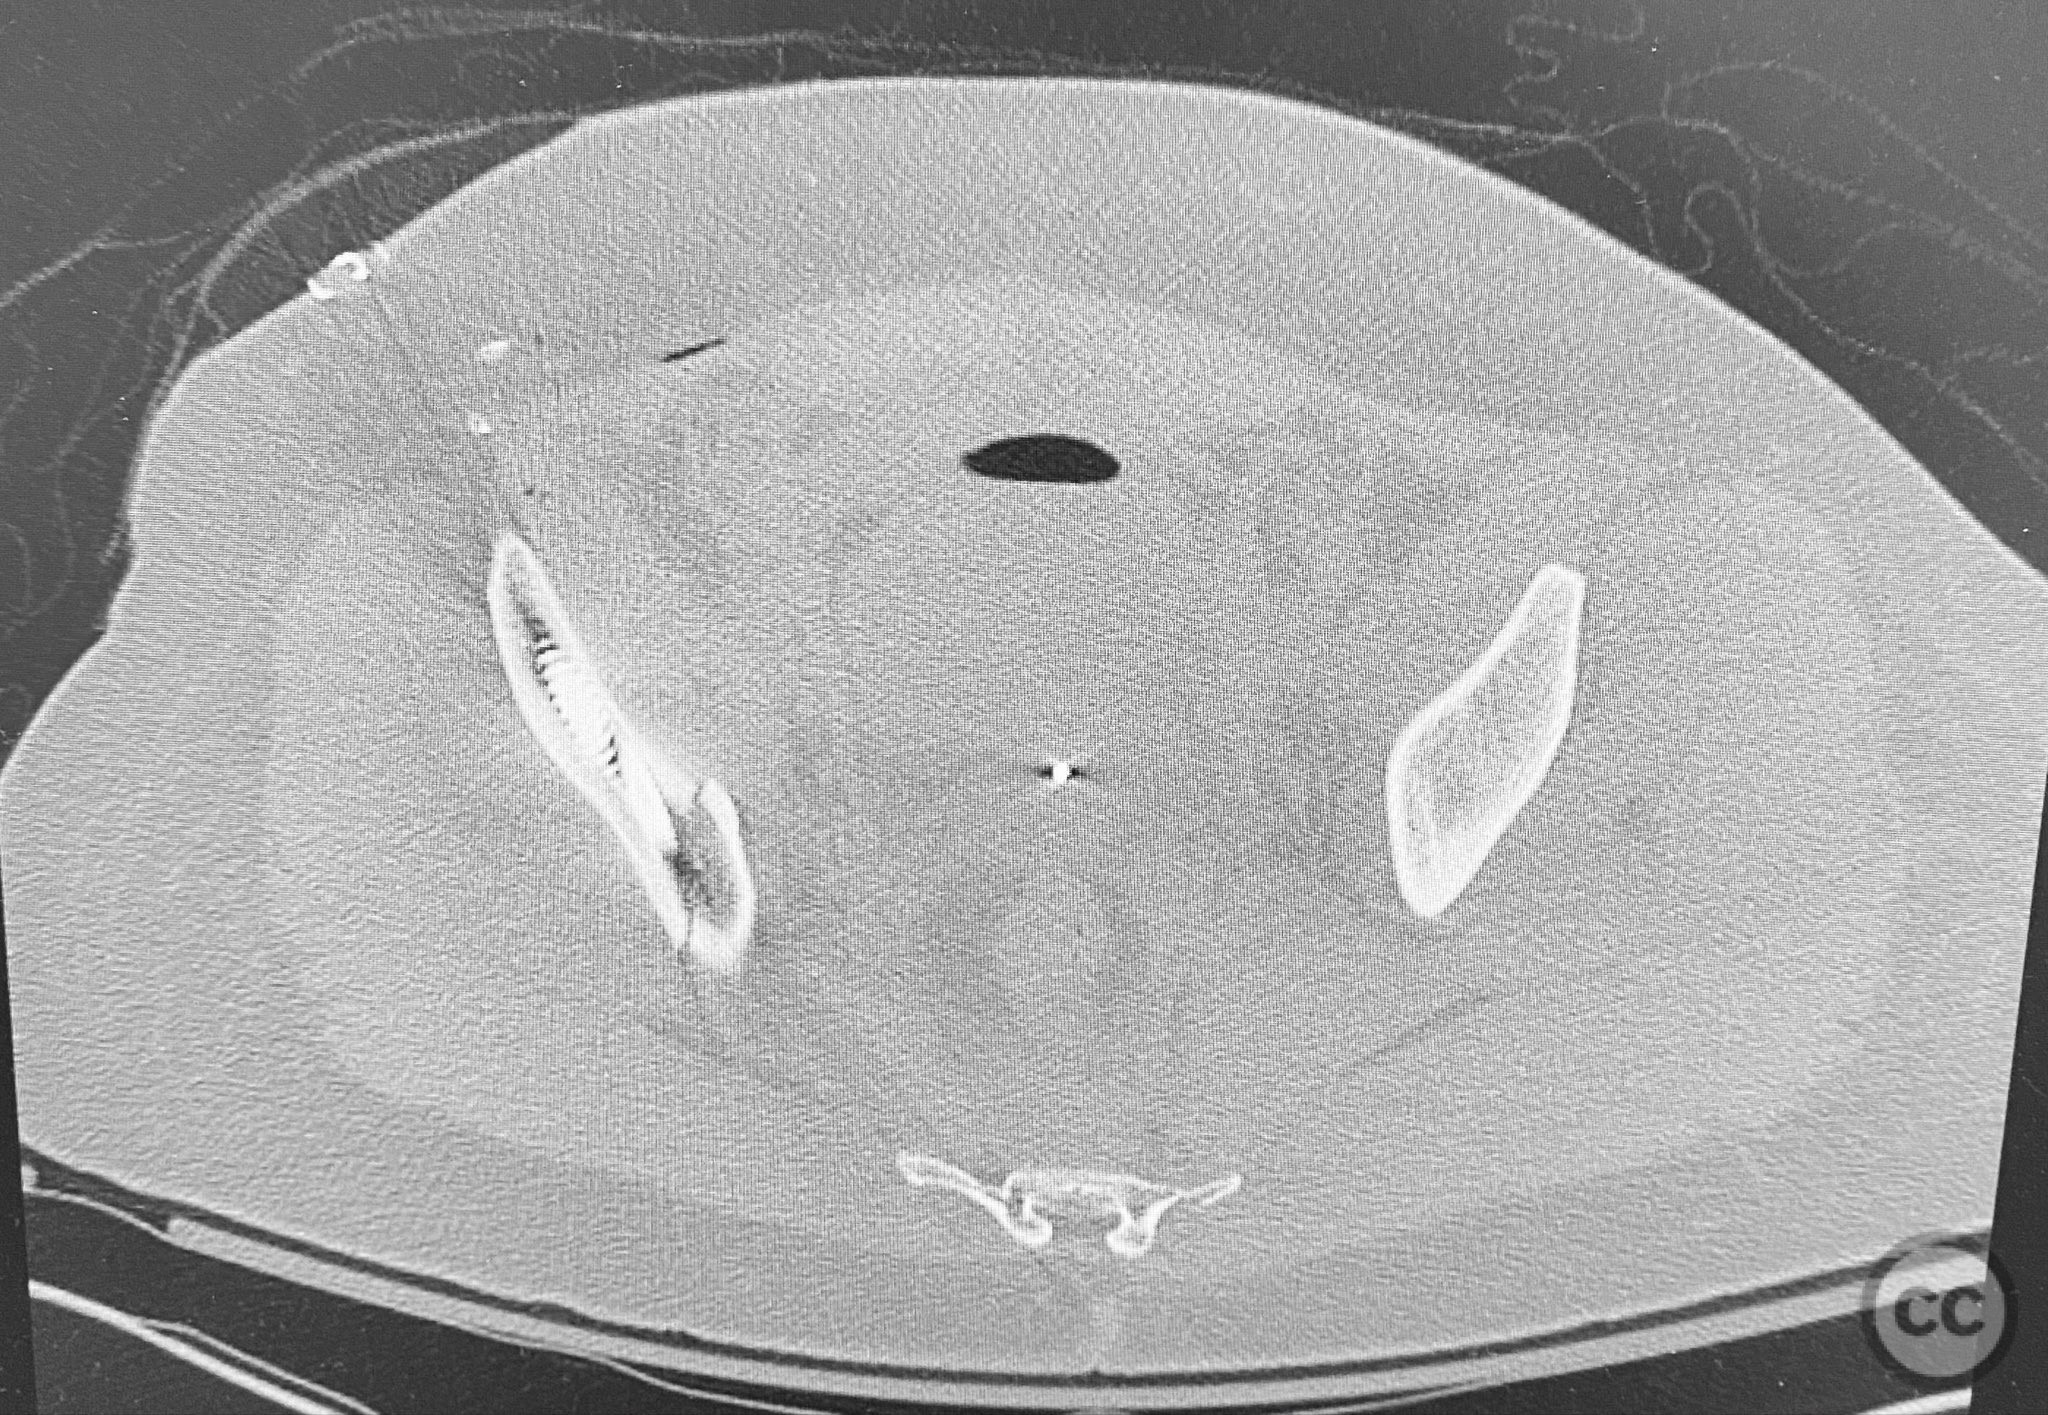

Clinical and radiological findings:  The patient presented following trauma with an unusual, significantly displaced right iliac fracture, accompanied by left-sided sacral and parasymphyseal ramus fractures. Initial AP pelvic radiography demonstrated the complex injury pattern. CT imaging provided detailed characterization of the iliac and sacral fractures, including assessment of displacement, bone quality, soft tissue status, and overall body habitus. No neurovascular compromise was reported. AO/OTA classification: Right iliac fracture 61B2.3 (partial unstable, lateral compression injury), left sacral fracture Denis zone I, left parasymphyseal ramus fracture.

Anatomical surgical approach:  A standard anterior ilioinguinal approach was utilized for the right iliac fracture. Dissection proceeded through the skin and subcutis, with identification and protection of the lateral femoral cutaneous nerve. The external oblique aponeurosis was incised, and the iliacus muscle was elevated subperiosteally from the internal iliac fossa to expose the fracture site. Reduction was achieved under direct visualization, followed by internal fixation with a contoured plate and pelvic brim cancellous screws, ensuring all implants were contained within the osseous fixation pathway. The left sacral fracture was stabilized percutaneously under fluoroscopic guidance.

Bilateral distal femoral traction resulted in excellent reduction of the sacral fracture but did not adequately reduce the iliac displacement. Percutaneous fixation of the sacrum was performed first, followed by open reduction of the iliac fracture. Intraoperative imaging confirmed that all implants were fully contained within the available osseous corridors, avoiding extraosseous penetration. The complexity of the iliac fracture required careful anatomical reduction and implant placement along the pelvic brim.

Orthopaedic implants used:   Pelvic brim contoured plate, cancellous screws, percutaneous sacral screw(s)